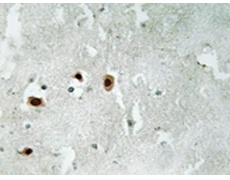

IHC positive control: |

Human brain tissue |